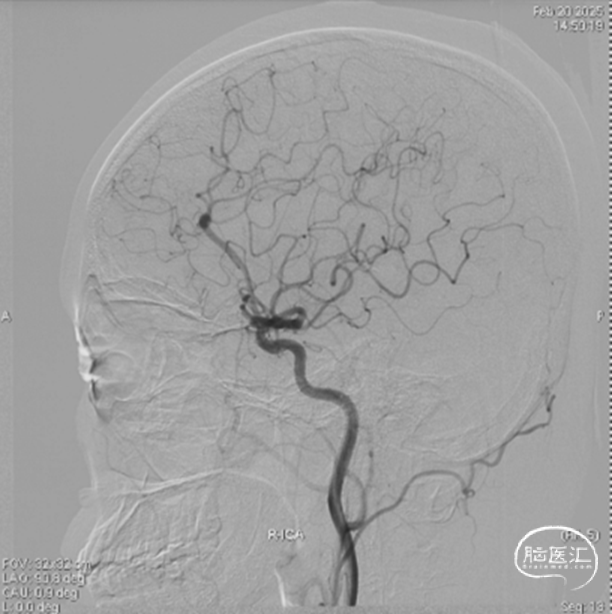

右侧颈内侧位造影

载瘤动脉远端血管直径:2.1mm

载瘤动脉近端血管直径:1.8mm

动脉瘤尺寸:瘤颈4.69mm,大小3.25mm*4.21mm*4.24mm;指向右上

近端狭窄:最窄处:0.53mm,远心端2.1mm,近心端2.2mm,长度11.23mm